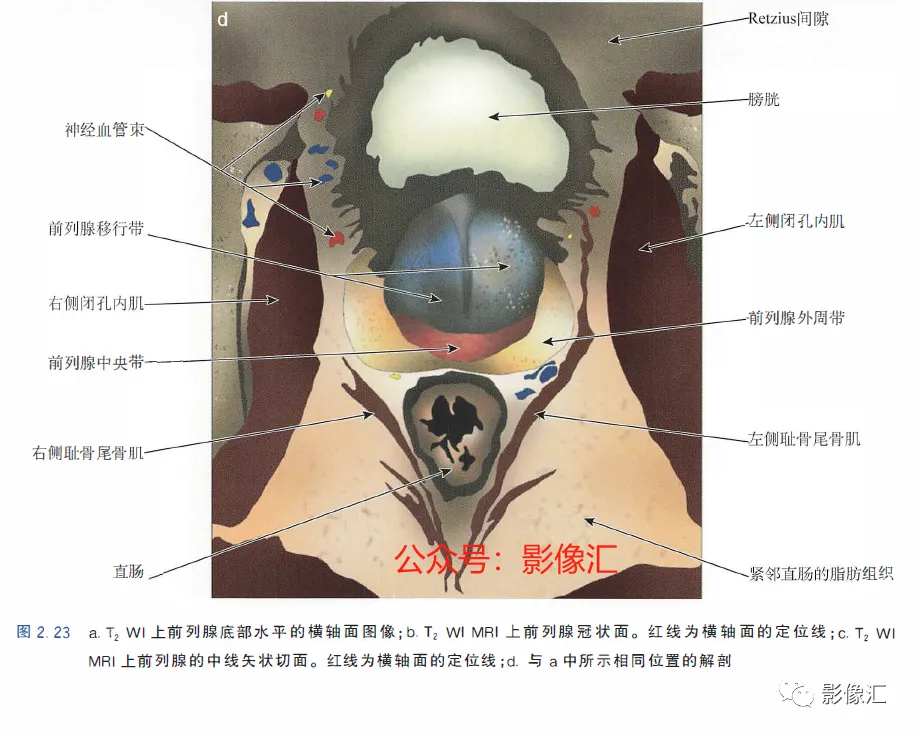

5. 前列腺底部水平的横轴面(图2.23)